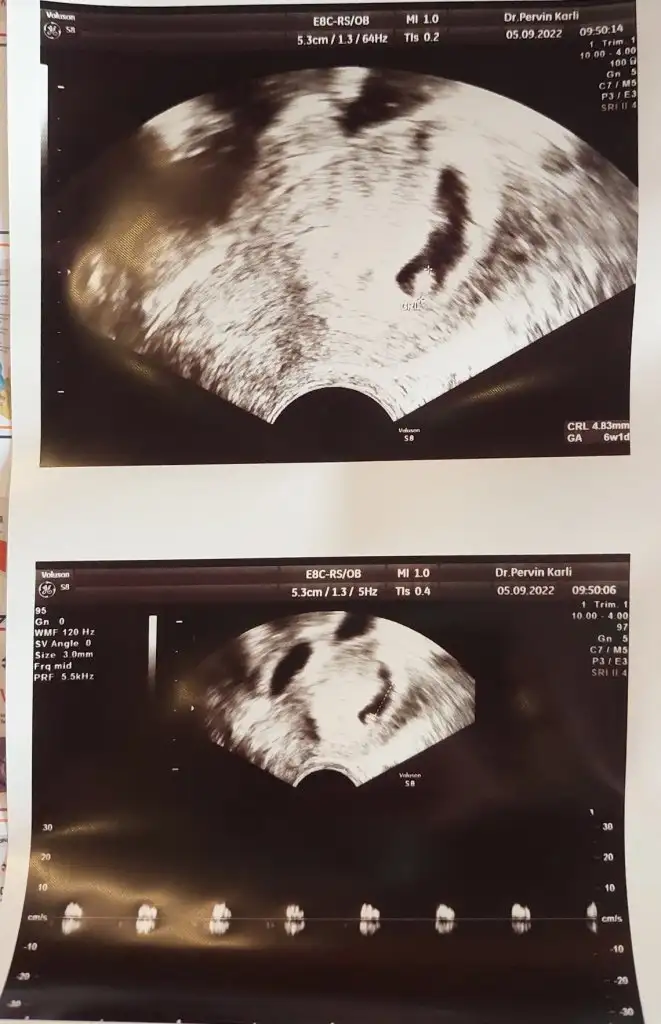

Canım hayırlı olsun sağlıkla kucağına alKızlar fazla ağrım olunca dayanamadım doktora gittim 5 + 2 olan bebeğe 6+0 dedi anlamadım bişey Ama bir sorun gözükmüyor dedi çok şükür gerçi ağzından zorla laf alıyorum çok tatmin olamadım ama şükür yine de . Bakın bugünkü hali . @Evdekikadin sanırım tek bebek bu arada yine tek çıktı